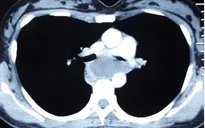

Kết quả chụp cắt lớp vi tính ngực thấy: 2 bệnh nhân có nhiều kén khí đỉnh phổi phải và kén khí phổi phải. Kết quả đo chức năng hô hấp bệnh nhân bị tắc nghẽn đường dẫn khí nhỏ.

Sau khi hội chẩn, bệnh nhân được chỉ định phẫu thuật nội soi vào khoang màng phổi phải bằng ba lỗ trocar, quan sát thấy kén khí ở thùy trên cực lớn (10 x 5cm) cùng nhiều kén nhỏ khác đẩy làm xẹp phổi phải của bệnh nhân. Do đó, bác sĩ quyết định cắt kén khí qua nội soi.